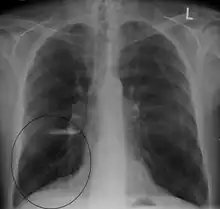

A chest X-ray and complete blood count may be useful to exclude other conditions at the time of diagnosis.[82] Characteristic signs on X-ray are hyperinflated lungs, a flattened diaphragm, increased retrosternal airspace, and bullae, while it can help exclude other lung diseases, such as pneumonia, pulmonary edema, or a pneumothorax.[83] A high-resolution CT scan of the chest may show the distribution of emphysema throughout the lungs and can also be useful to exclude other lung diseases.[25] Unless surgery is planned, however, this rarely affects management.[25] A saber-sheath trachea deformity may also be present.[84] An analysis of arterial blood is used to determine the need for oxygen; this is recommended in those with an FEV1 less than 35% predicted, those with a peripheral oxygen saturation less than 92%, and those with symptoms of congestive heart failure.[24] In areas of the world where alpha-1 antitrypsin deficiency is common, people with COPD (particularly those below the age of 45 and with emphysema affecting the lower parts of the lungs) should be considered for testing.[24]

- Lung bulla as seen on chest X-ray in a person with severe COPD